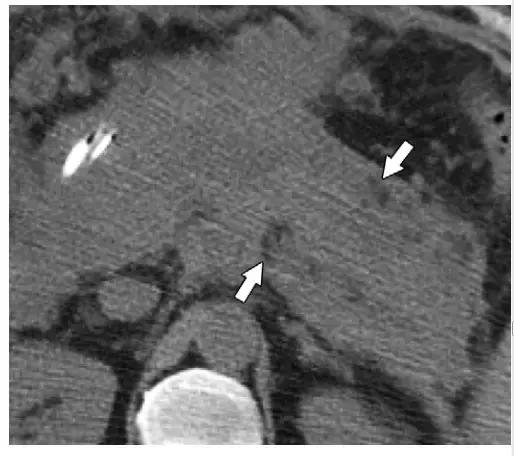

4 周以后,ANC 逐渐形成成熟的壁,进展为 WON。同假性囊肿相似,WON 包括液性物质和可明显强化的厚壁。但与假性囊肿不同的是,WON 含有坏死脂肪或胰腺组织,在增强 CT 和 MR 图像中表现为液体内含有非液性成分(图 3c,10)。

WON 可存在于胰腺实质,但更常见于胰周,也可同时累及胰腺和胰周(图 10)。有研究表明,对于病程超过 4 周胰腺炎,MR 的评估能力高于 CT。

图 10 48 岁坏死性胰腺炎女性患者 2 个月内的演变过程。 a 1 周:轴位增强 CT 示胰颈坏死(*)。 b 2 周:轴位增强 CT 示新发胰颈(*)坏死相连的胰周(箭头)坏死,征象符合 ANC。 c 3 周:周围 T2WI MR 图像更清晰的显示了 ANC(*)的内容物,包括液性高信号和非液性坏死物,后者又包括胰颈和胰体的坏死(箭头)。注意局部壁形成。 d 5 周:轴位增强 CT 示成熟壁形成,符合 WON(*)的诊断。 e 囊肿胃引流术和清创术中内镜可见 WON 排出的坏死物(箭头)。 f 7 周:术后增强轴位 CT 图像可见 WON 已成功清除,可见双尾支架影